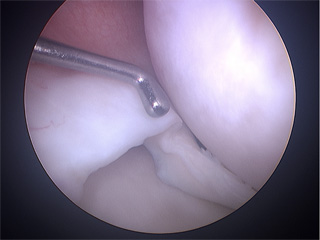

Arthroscopy is a common surgical procedure which lets orthopaedic surgeons to see inside the knee joint. It is done under spinal anesthesia and through small incisions around your knee, so that the joint does not have to be opened up fully. The surgeon will make two small cuts (less than 6 mm.) on both sides next to the patellar tendon. A tiny camera will be inserted into your knee through one of the cuts. The camera is attached to a video monitor, thus the image is sent to the monitor and surgeon can see the structures of the knee joint in great detail as the surgical technique procedure.

Knee arthroscopic procedures should begin with an exploration to make a diagnosis. Doctor should examine carefully every joint in a systemic way, in order to bring to light undiagnosed injuries by imaging test.